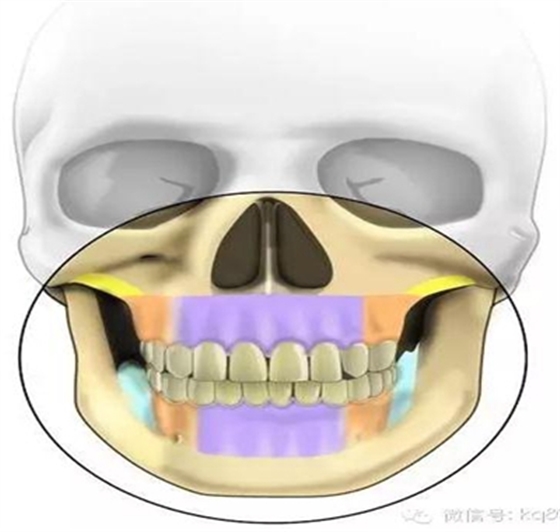

根據(jù)骨類型,骨密度,牙根間距、粘膜厚度不同,把上下頜分為不同區(qū)域,分別用紫橙藍(lán)黃四種顏色標(biāo)記,這些區(qū)域就是傳統(tǒng)的可植入部位,每個(gè)部位所選擇的支抗釘也相應(yīng)會(huì)有所差異

上下頜前牙區(qū)(11、12或者23之間,具體根據(jù)CT和患者頜關(guān)系決定):

上下頜磨牙后區(qū)(56之間居多):

顴牙槽嵴(成人多在67之間,未成年多在56之間或6上方,根據(jù)CT確定)